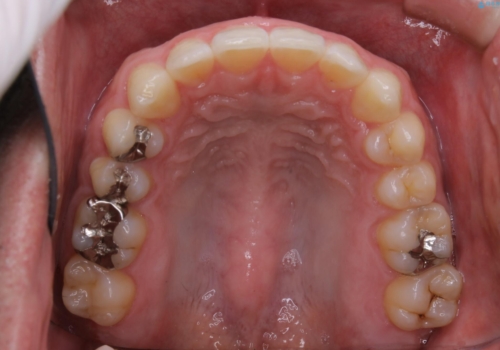

- 全体的に歯と歯の間に隙間があるのが気になるとのことで来院されました。インビザラインでの矯正治療をご希望されました。

隙間については、前歯と奥歯に多数あります。また、上下前歯は、外側に少し倒れているため隙間を閉じつつ、前歯を内側に引っ込めて並べることになりました。

インビザライン・ライトにて矯正治療を行うことになりました。